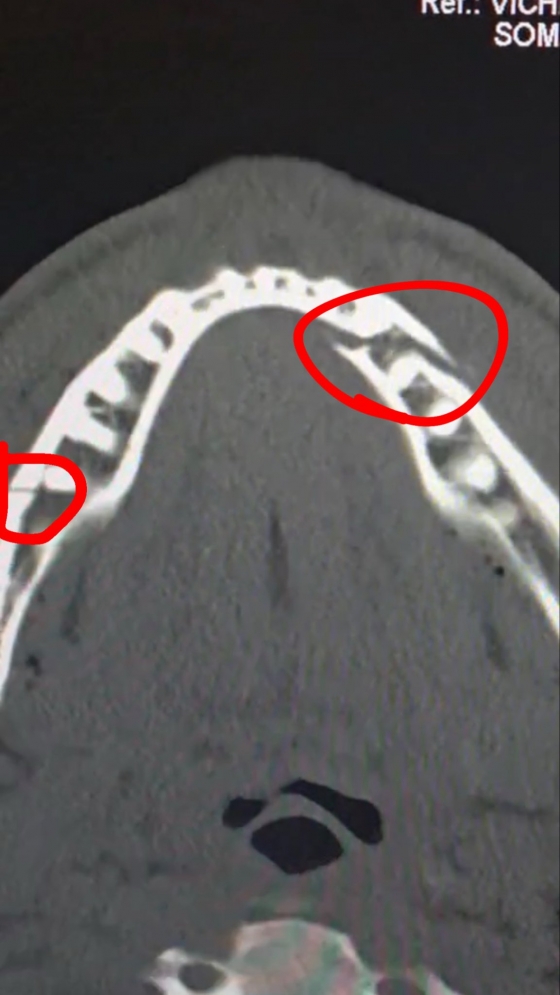

조슈아 측 프로모터 에디 헌 역시 조작설에 전면 반박했다. 헌은 "우리는 배우가 아니다. 이 경기는 100% 리얼이었다"며 "폴의 턱뼈가 두 곳이나 부러지고 치아가 여러 개 빠진 것이 그 증거다. 만약 조슈아의 초반 오른손 펀치가 제대로 꽂혔다면 그때 이미 턱이 나갔을 것"이라고 말했다. 이어 "턱이 부러져 다시는 링에 서지 못하는 복서들이 얼마나 많은지 아느냐"며 폴이 입은 부상의 심각성을 강조했다. 실제로 폴은 턱에 티타늄 플레이트 2개를 삽입하는 수술을 받았으며, 일부 치아를 제거하고 최소 일주일간 유동식만 섭취해야 하는 상태다.